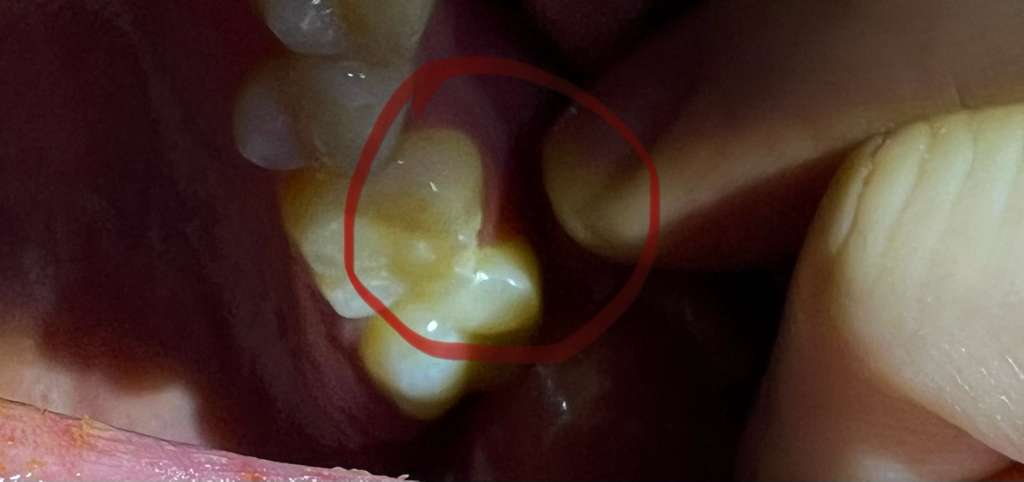

어금니 충치치료로 인레이랑 레진 몇군데를 하였는데

그 부분이 손상이 된것인지

아니면 새롭게 깨진것인지 모르겠습니다

• 2번 째 사진

치아가 강한 힘으로 인해서 파절된 것으로 보입니다 치아에 가해지는 힘을 줄이는 것이 좋으며 파절된 부위는 치과용 재료로 충전을 해 줄 수 있습니다 자세한 확인을 위해서 치과에서 진료를 받아 보세요

말씀하신 것처럼 어금니 옆면 표면이 깨져나가 있습니다. 치아의 가장 바깥층을 법랑질이라고 하는데 법랑질 부위가 없거나 얇아지면 내부 상아질, 치수(치아 신경)가 드러나면서 시릴 수 있습니다. 시간이 지남에 따라 경화상아질이라는 새로운 층이 생겨 시린 증상이 너무 심하지 않도록 치아 자체가 방어벽을 형성하기도 하지만 시린 증상이 심하다면 치과에서 치료를 받는 편이 좋습니다

해당 부위는 아주 깊거나 크게 깨지지는 않았으나 충전재료가 잘 떨어지는 위치이므로 치과의사의 판단에 따라 다를 수는 있으나 레진으로 떼워줄 수도 있고, 크라운을 하자고 할 수도 있습니다.